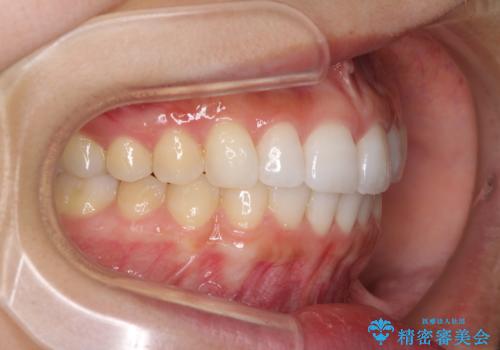

結婚式までに前歯を整えたいとのことでしたが、インビザラインでは先に奥歯を移動させてから前歯を動かすため、間に合わない可能性がありました。しかし、結婚式までに期間があったことと、マウスピースをしっかりと装着してくださったことで、十分な歯列に整えることができました。

楽しく通院していただき、辛いと思っていた治療もあっという間であったそうで、患者様には大変満足していただきました。